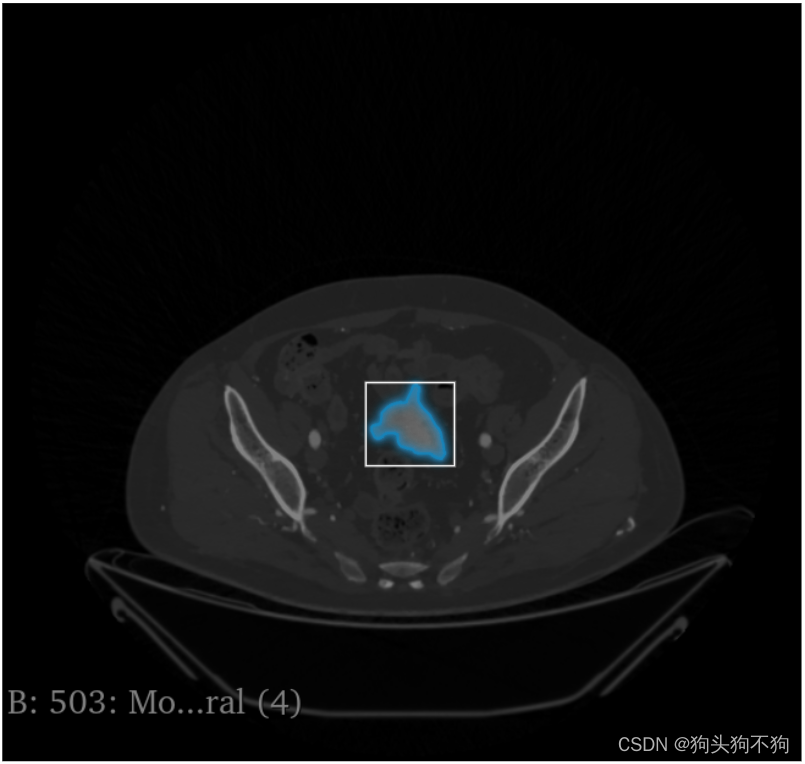

除了网站提供的图像之外,还支持自己上传图像,以人体的CT扫描图像为例

左侧选择栏给了三种模式,点击,框选,和整图分割

框选: